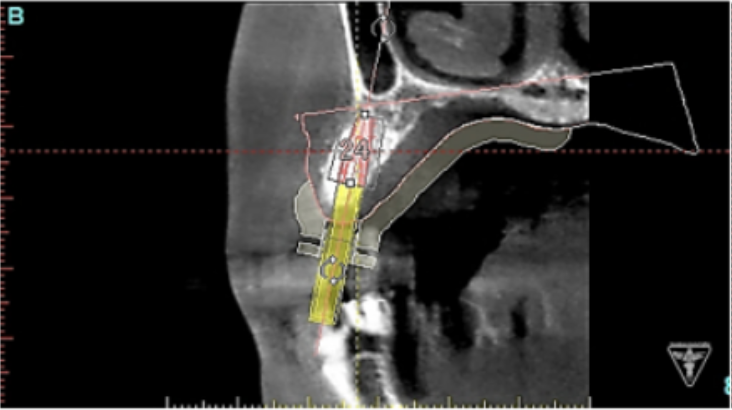

サージカルガイドの作成